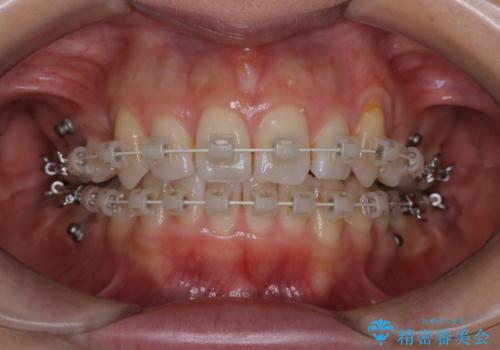

ワイヤー矯正中のPMTC

- ワイヤー矯正中に装置の周りの着色が気になるとのことで来院されました。PMTC30分コースを行いました。

ワイヤー矯正中も、歯の表面に着色(ステイン)が付着することがあります。着色(ステイン)が付着したままだと審美的な問題以外にも、虫歯を発見しずらいことや、細菌が繫殖しやすくなることがあります。クリーニングを行うことで、虫歯や歯周病予防に効果的だったり、もちろん見た目も審美的です。クリーニング後には、汚れが取り除かれ、お口の中がスッキリ・爽快感で気持ちがよくなります。矯正中も定期的にPMTCを行うことが大切です。